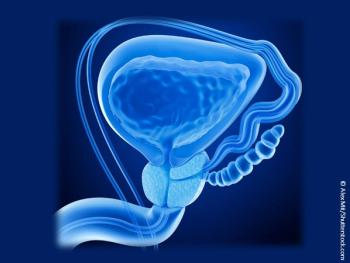

Take this quiz to test your knowledge of new findings for an age-old problem in men.

Slide Show: Get top-line results of 10 new studies on the most common non-skin cancer among US men.